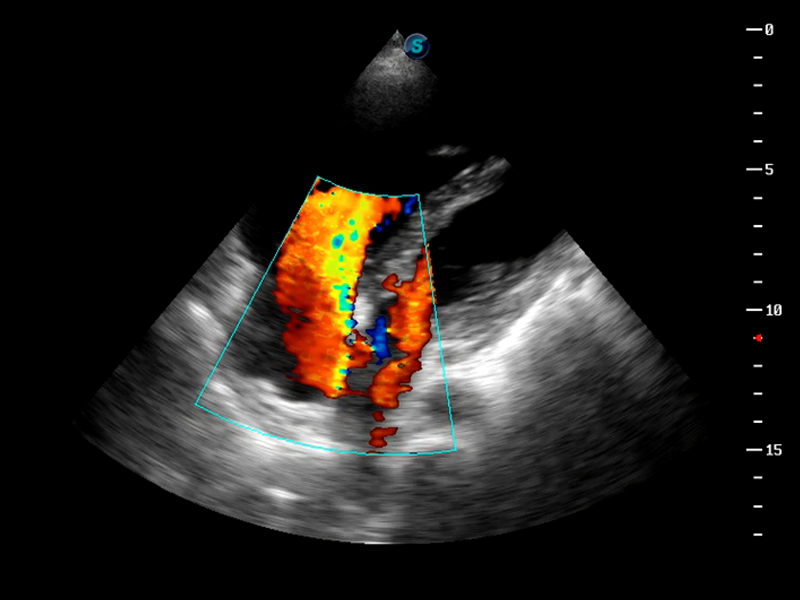

TDI组织多普勒成像

造影成像